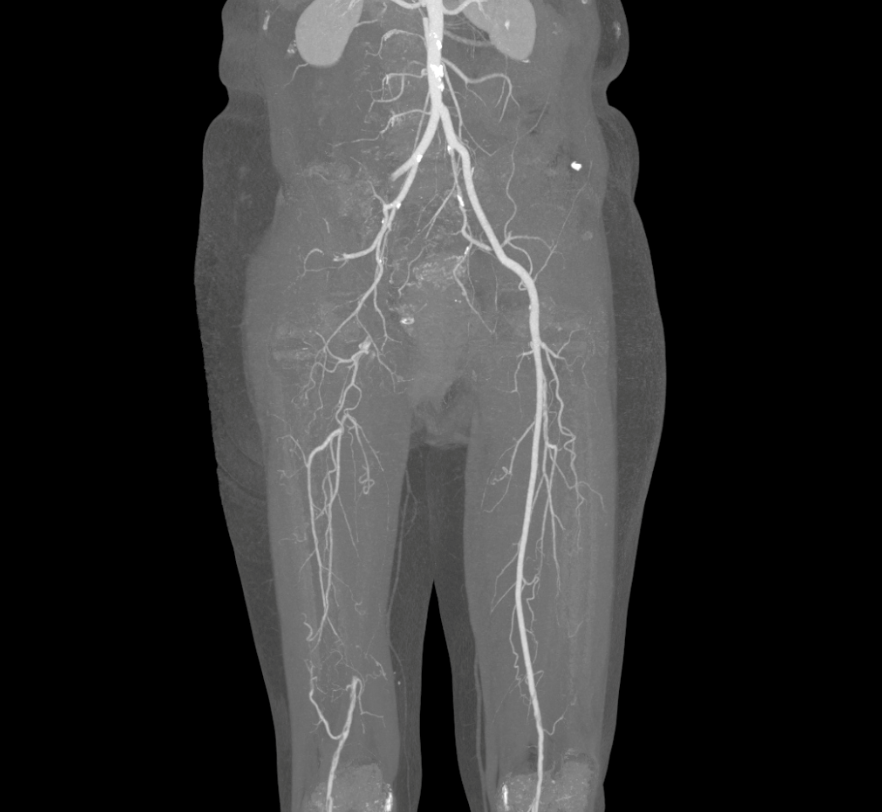

MSCT scan shows atherosclerosis and scattered thrombi in the lower extremity arteries. Photo: *Tam Anh General Hospital*

Doctor Pham Ngoc Minh Thuy, a cardiovascular surgeon at Tam Anh General Clinic in District 7, diagnosed Kieu with acute thrombosis on a background of chronic vascular disease (narrowing due to atherosclerosis). The blood clot completely blocked the artery, extending from the right external iliac artery to the entire right femoral artery and the blood vessels below. This caused severe blood deficiency in the right leg, risking limb necrosis without treatment.